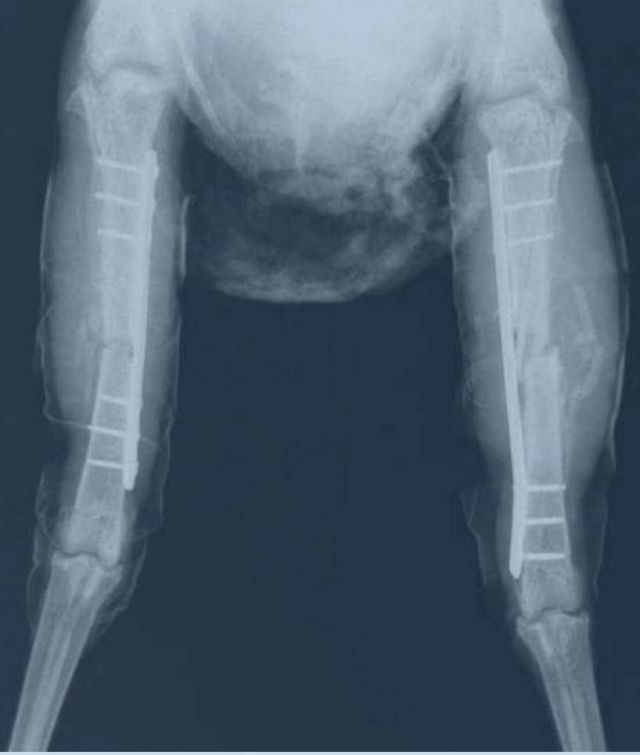

قدما الفرخة ليسكي بالأشعة

ولفت الطبيب المعالج، أنه كانت هناك معناه في إيجاد شرائح ومسامير بصغر ساق الدجاجة، وتم تركيب شريحتين وستة مسامير وهي الآن بصحة جيدة وسنقوم بإجراء عملية أخرى بعد شهر لفكها، وأن العملية الجراحية التي أجريت للدجاجة استغرقت ساعتين ونصف تقريباً.